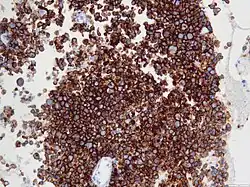

Die Diagnose wird mittels einer Biopsie gestellt. Als diagnostische Kriterien fordert die WHO den Nachweis typischer Zellen sowie der Expression des Zytokin-Rezeptors CD30. Prognostisch bedeutend ist der Nachweis der Anaplastic Lymphoma Kinase (ALK). Fast alle Fälle des ALCL im Kindesalter sind ALK-positiv.